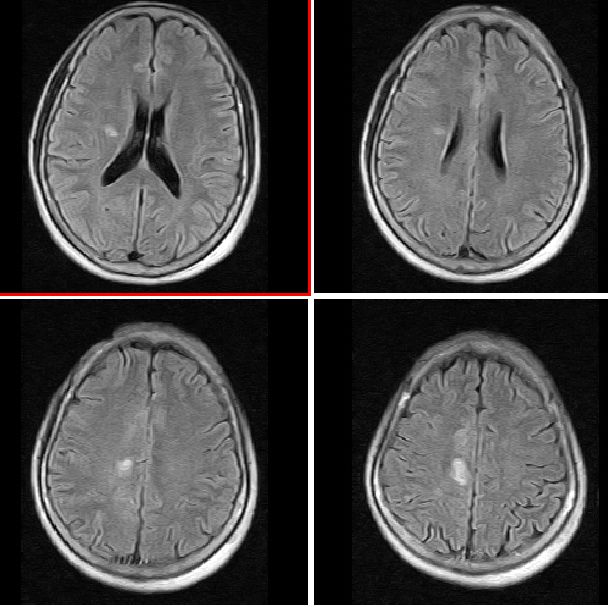

mri平扫

mr表现:中央旁小叶区病灶号不均匀性稍长t1、长t2信号,病灶周边见稍短t1信号环。右侧脑室体旁见点片状等t1、稍长t2信号影。flai序列各病灶均呈高信号。增强后右侧中央旁小叶区病灶呈不均匀性强化。